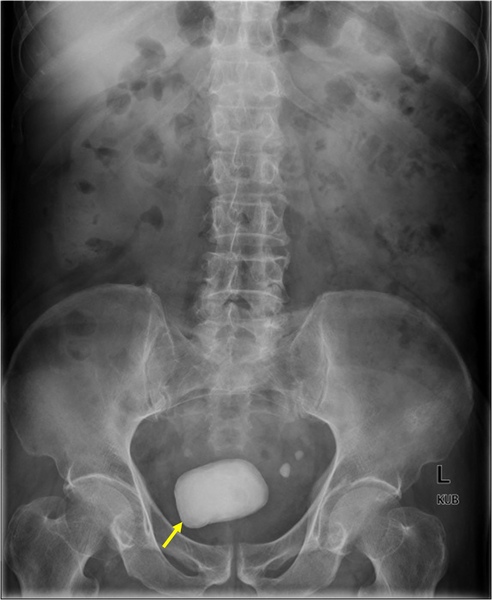

這張圖裡是位在膀胱的結石,好大一顆。